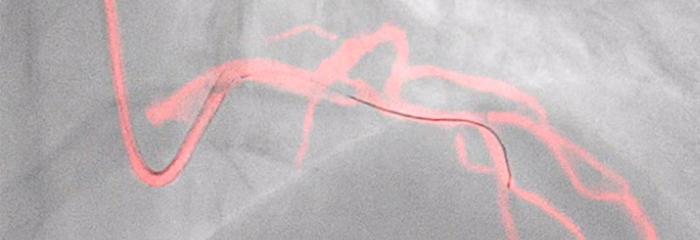

Dynamic Coronary Roadmap, a Philips-exclusive technology, creates a motion-compensated, real-time view of coronary arteries. Recent evidence demonstrates that DCR can reduce contrast agent by 28.8% during a PCI procedure. With DCR a highlighted coronary angiogram is superimposed on a live 2D fluoroscopic image, creating a colored roadmap that adjusts automatically, providing continuous visual feedback on positioning of wires and catheters.